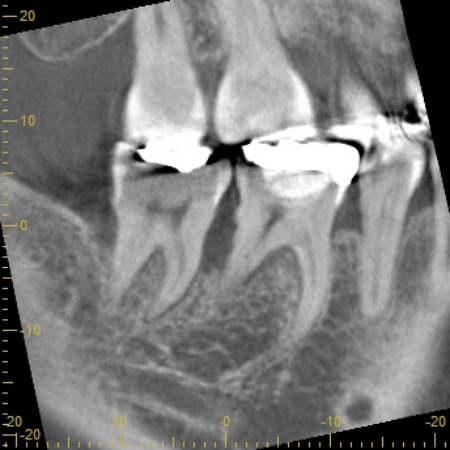

右上下の奥歯に対して、レントゲン撮影と歯間の溝の深さを測る歯周ポケット検査をしたところ、重度の歯周病が認められました。歯を支える骨が大幅に失われ、歯がぐらぐらしている状態です。

また左上下の奥歯についても同様で、重度の歯周病が進行しています。

続いて上下左右の奥歯に対して、失われた歯を支える骨や歯根膜(歯を支える薄い膜)を再生させるため、骨の再生を促す材料などを充填する歯周組織再生療法を実施しました。